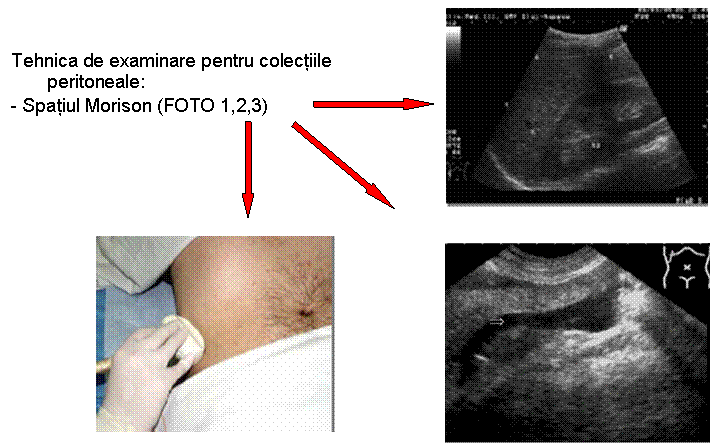

TRAUMATISM ABDOMINAL EXAMINARE FAST